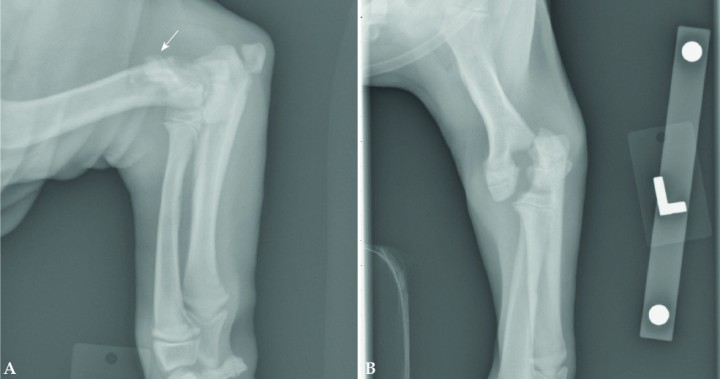

<p>Imágenes radiográficas de un cachorro de 6 meses con una fractura de la tuberosidad tibial (TT). Véase el desplazamiento proximal de la tuberosidad tibial (Fig. 3A) como consecuencia de la tracción del ligamento rotuliano. Es muy importante evaluar la proyección craneocaudal (Fig. 3B) para un completo estudio radiológico. Si se compara con el miembro derecho se podría apreciar una localización de la tuberosidad tibial más proximal, así como un desplazamiento proximal de la rótula. Su tratamiento es generalmente quirúrgico con la estabilización de la TT con agujas de Kirschner y un cerclaje (banda de tensión). En animales muy jóvenes puede ser necesaria la retirada de los implantes para evitar un cierre fisario prematuro y desplazamiento distal de la TT.</p>

Figura 3

Imágenes radiográficas de un cachorro de 6 meses con una fractura de la tuberosidad tibial (TT). Véase el desplazamiento proximal de la tuberosidad tibial (Fig. 3A) como consecuencia de la tracción del ligamento rotuliano. Es muy importante evaluar la proyección craneocaudal (Fig. 3B) para un completo estudio radiológico. Si se compara con el miembro derecho se podría apreciar una localización de la tuberosidad tibial más proximal, así como un desplazamiento proximal de la rótula. Su tratamiento es generalmente quirúrgico con la estabilización de la TT con agujas de Kirschner y un cerclaje (banda de tensión). En animales muy jóvenes puede ser necesaria la retirada de los implantes para evitar un cierre fisario prematuro y desplazamiento distal de la TT.

<p>Fractura a nivel de la línea de crecimiento de la tibia proximal en un cachorro de 4,5 meses de edad. En la proyección mediolateral (Fig. 4A) se puede observar que el fragmento proximal de la fractura lo componen la meseta tibial y la tuberosidad tibial. No existe línea de fractura entre la meseta tibial y la tuberosidad tibial. Nótese el desplazamiento caudal de la meseta tibial en relación al resto de la tibia. En la proyección craneocaudal (Fig. 4B) se observa un incremento de la opacidad de los tejidos blandos a nivel de la línea de crecimiento, aunque no existe desplazamiento de la fractura medio-lateralmente.</p>

Figura 4

Fractura a nivel de la línea de crecimiento de la tibia proximal en un cachorro de 4,5 meses de edad. En la proyección mediolateral (Fig. 4A) se puede observar que el fragmento proximal de la fractura lo componen la meseta tibial y la tuberosidad tibial. No existe línea de fractura entre la meseta tibial y la tuberosidad tibial. Nótese el desplazamiento caudal de la meseta tibial en relación al resto de la tibia. En la proyección craneocaudal (Fig. 4B) se observa un incremento de la opacidad de los tejidos blandos a nivel de la línea de crecimiento, aunque no existe desplazamiento de la fractura medio-lateralmente.